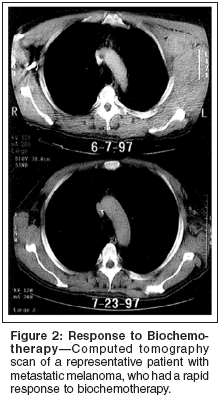

Phase II studies of cisplatin-basedbiochemotherapy regimens haveshown overall response rates rangingfrom 40% to 60%, with complete remissionrates on the order of 10% to20%.[22-34] Durable remissions exceeding5 years were seen in approximately5% to 10% of patients. Ofinterest, relapses occurring beyond2 years were distinctly uncommon,suggesting that these patients exhibitingdurable responses may be"cured."[22,24-26] Furthermore, response to biochemotherapy is usuallyrapid and observed after the first cycle.A representative case is shown inFigure 2.

The results of select phase II studieswith IL-2 administered intravenouslyare shown in Table 1.[22-28,32-34]One of the most popular regimensdeveloped at M. D. Anderson CancerCenter is the CVD regimen administeredconcurrently with IL-2 and IFNalfafor a maximum of six cycles.Tumor responses were observed in34 of 53 patients (64%), with 20%complete responses and 9% durablecomplete responses.[25] In anotherstudy, this regimen was modified inan effort to reduce toxicity. Modificationsincluded antibiotic and granulocytecolony-stimulating factor (G-CSF[Neupogen]) prophylaxis, prohibitionof long-term central venous access,and restriction to a maximum of fourcycles of therapy. Tumor responseswere seen in 19 of 40 evaluable patients(response rate: 48%) including8 complete responses.[28] Biochemotherapywas also evaluated as secondlinetherapy in melanoma patients andfound to have negligible activity inthis patient population, producing anoverall response rate of only 6% comparedwith 37% in previously untreatedpatients.[28]O'Day et al recently reported theuse of IL-2 and granulocyte macrophagecolony-stimulating factor (GMCSF[Leukine]) as maintenancetherapy in patients who achieved apartial response or stable disease onbiochemotherapy. Preliminary resultsof this pilot experience were encouragingin terms of progression-free andoverall survival, compared with historicalcontrols.[35] A larger phase IImulticenter trial has been initiated inan effort to confirm these results.